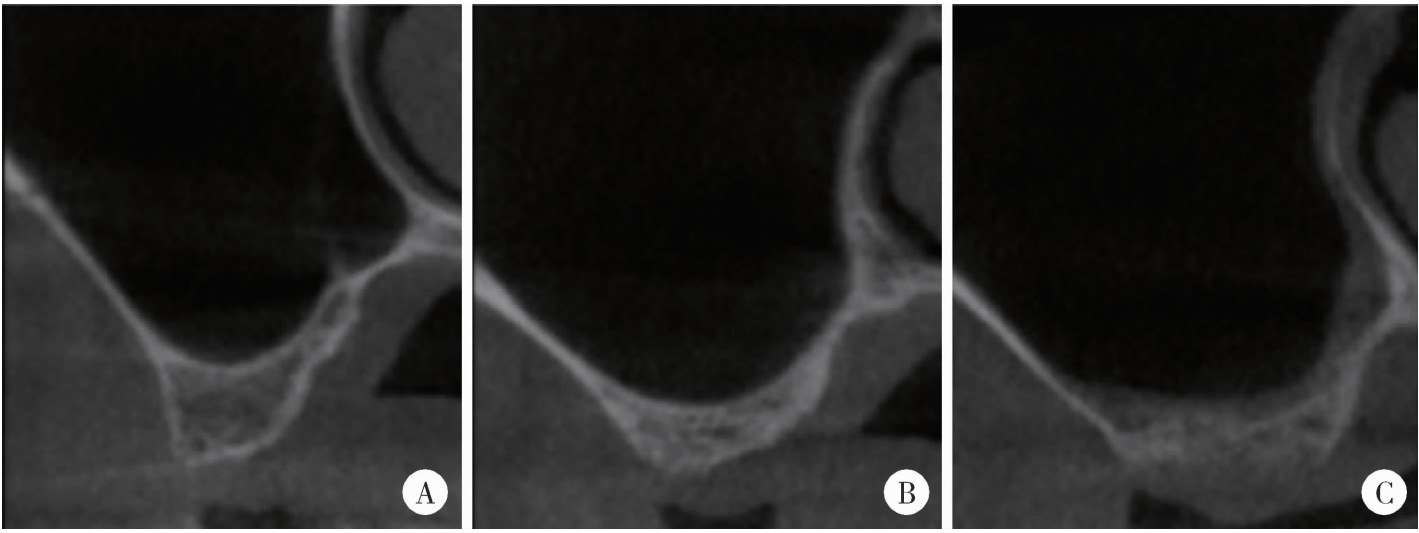

Figure 3

Morphology of maxillary sinus in the buccal and palatal directions A, taper; B, round; C, flat."